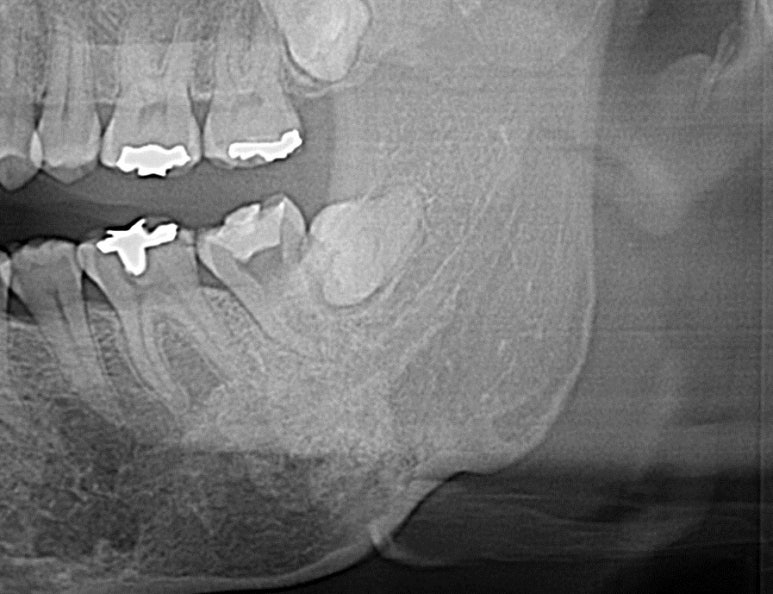

발치 전 사진이 없어서 아쉽지만... 이렇게 한 개 치아를 반드시 발치해야하고 주변치아들이 비뚤다면 정말 교정이 답이 될 수 있다는 생각이 든다. 잇몸이 너무 좋지 않아서 잇몸공간이 눈에 띄기는 하지만 이후 치주 관리도 잘하시고 유지장치로 앞니끼리 고정되어 있으니 예상보다 오래 잘 쓰시고 계신다..